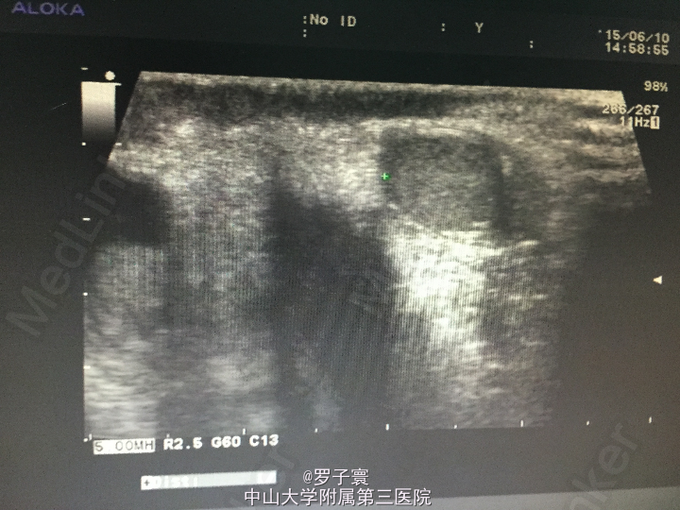

查体:阴茎呈男童外观,包茎,左侧阴囊空虚,未触及任何内容物,左侧腹股沟可触及睾丸样团块,质地软,大小1.4*0.6cm,无触痛,无粘连,站立活动后右侧阴囊可触及质软肿物,透过试验阳性,可扪及右侧睾丸,大小约1.5*0.8cm,触诊质地软,表面光滑,无硬结,无压痛,附睾、精索触诊不满意。生殖系彩超(我院,2015-06-10):双侧阴囊内睾丸缺如;双侧腹股沟部隐睾(左侧活动度大);右侧睾丸鞘膜积液。